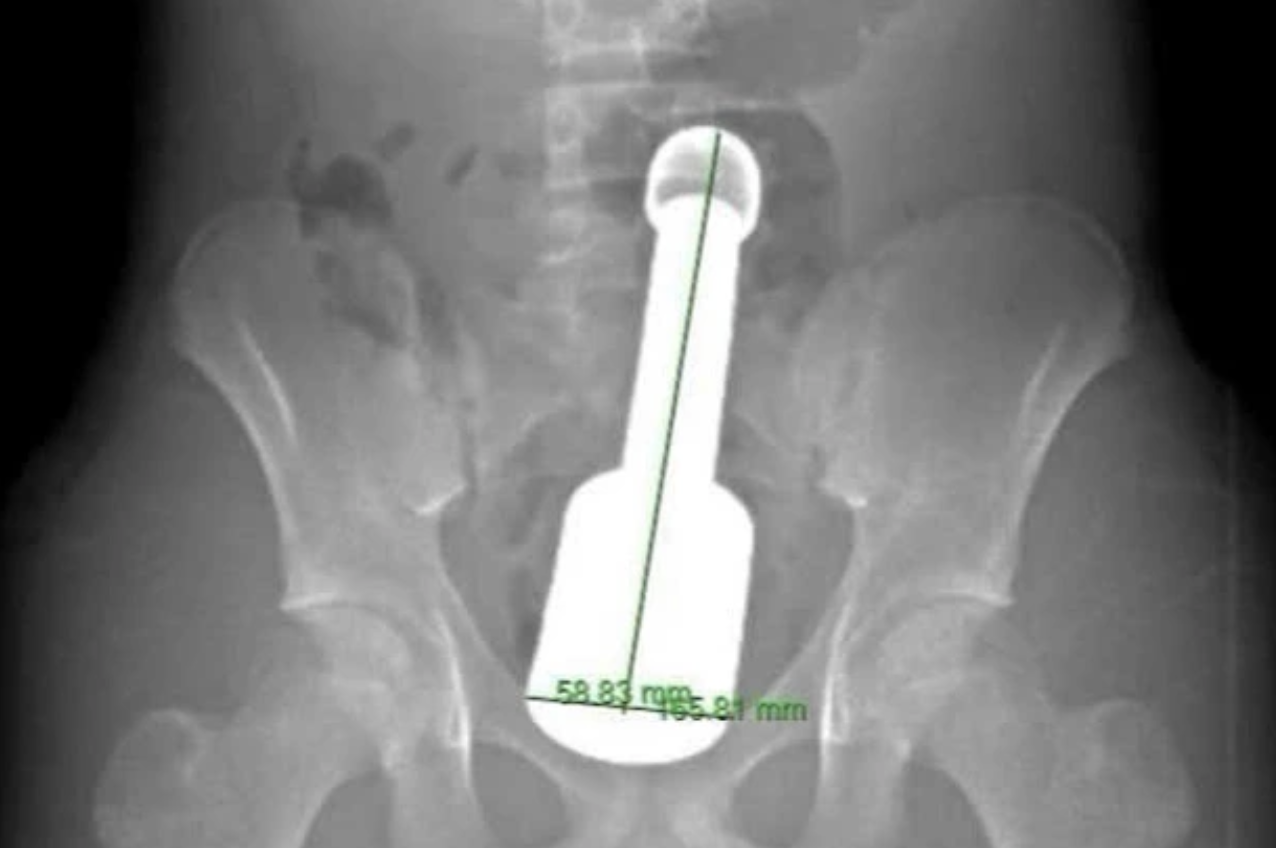

Bệnh viện Đa khoa Hà Đông, Hà Nội vừa cấp cứu, lấy thành công một dị vật kim loại kích thước lớn (chiếc chày dài 18cm) ra khỏi trực tràng bệnh nhân N.K.N. (15 tuổi).

Hình ảnh chụp X-quang và dị vật được lấy ra khỏi hậu môn của bệnh nhân - Ảnh: BVCC

Bệnh nhân nhập viện trong tình trạng đau tức dữ dội vùng hạ vị. Kết quả chẩn đoán hình ảnh cho thấy một Thiếu niên 15 tuổi nhập viện vì kẹt đồ chơi tình dục trong hậu môn